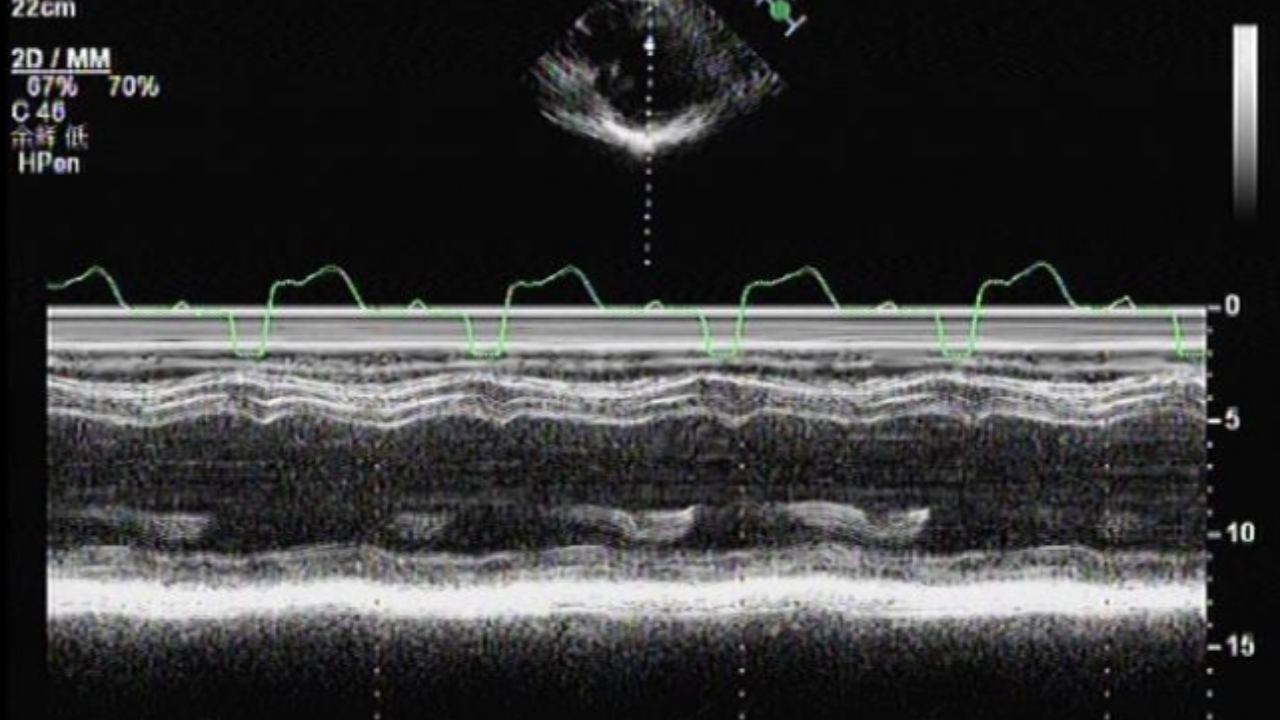

心超动图2: